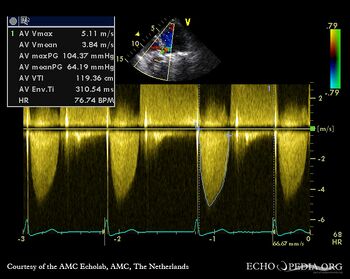

| A5CH: moderate aortic regurgitation | Continuous-wave signal of severe aortic stenosis |